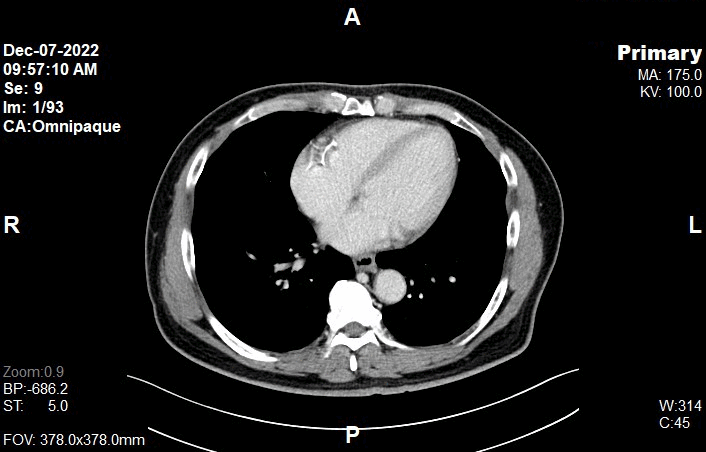

Appearance of CT Liver - Late Arterial Phase (LAP) Images

Appearance of CT Liver - Portal Venous Phase (PVP) Images